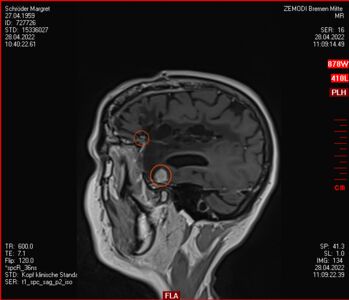

Zu meinem Geburtstag am 27.4. habe ich sehr schöne Geschenke bekommen und kann mich auch über meinen bunten Garten freuen, im Herbst gab es ein Tulpen-Sonderangebot, dem konnte ich nicht wiederstehen! Und nun ist das Ergebnis zu sehen. Am 28. April war wieder mal MRT-Termin. Leider hat es an dem Tag eine Vertretung des auswertenden Arztes gegeben, die Ärztin war super freundlich aber hat keine ganz konkreten Aussagen machen können, aber sie hat mir 2 CDs gebrannt, ich konnte eine gleich bei den Neurochirurgischen Ambulanz abgeben und eine mit nach Hause nehmen. Mein Blick auf die Bilder hat eine nazu unveränderte Lage gezeigt.

Heute war der Termin beim Chirurgen, leider schon um 9:00 Uhr und natürlich wollte ich die knapp 20 km mit dem Rad zurück legen, Stephan wollte gerne mitkommen. Leider war die bereits abgegebenen CD nicht eingelesen worden und so musste erstmal die Datenverarbeitung arbeiten und wir warten, bis wir eine Auskunft bekommen konnten. Fazit: Der bestehende Tumor ist kaum gewachsen. Aber es hat sich leider ein 2. Fund ergeben, sehr klein aber deutlich sichtbar. Aber Maßnahmen sind erstmal nicht notwendig.